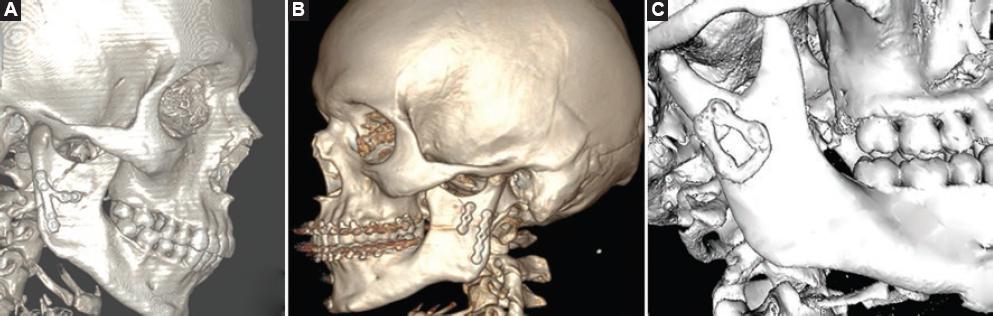

There are various designs of plates as osteosynthesis material used to perform the internal fixation. The five main designs for performing osteosynthesis, as required on a case-by-case basis, are: (1) straight standard plate, (2) inverted Y plate, (3) delta plate, (4) trapezoidal plate, and (5) rectangular plate. The use of each of them depends on the fracture to be reduced, being the straight plate the most used, due to its high resistance29,30 (Fig. 3). Strut plates are also a three-dimensional plate option for transoral endoscopically assisted approaches, providing intraoperative handling and fitting accuracy, precluding complications such as plate fatigue fractures31.